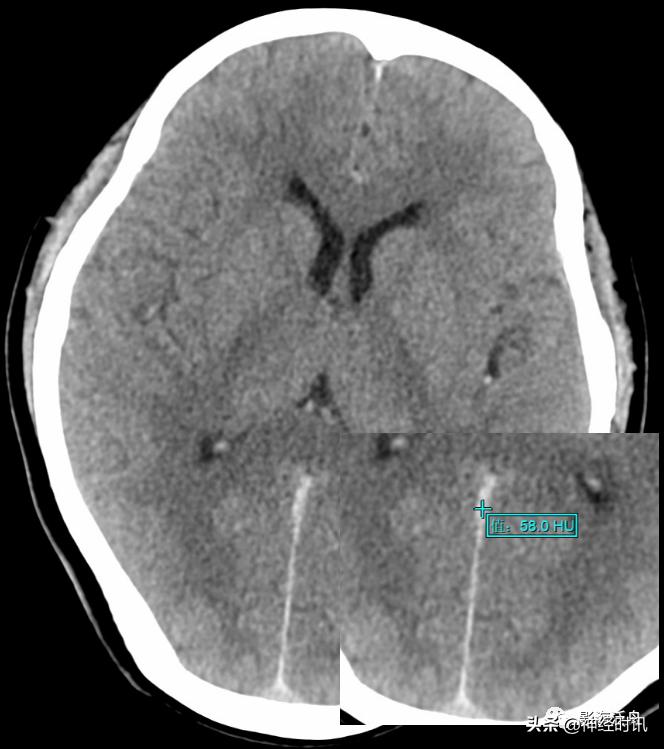

高空坠落伤患者,外伤后不到2h行头颅CT检查,整个片子中只有右侧环池可见斑片状高密度影,CT值57HU,36小时后复查,病灶密度减低,CT值约41HU,本例为少量蛛血的典型病例。

由于脑脊液的流动冲刷作用,蛛网膜下腔少量出血所形成的小血肿远没有脑实质内的血肿稳定,即便在外伤后第一个24h内,其CT值也很难超过60HU(课本上讲的脑内血肿极限CT值为94HU,平时工作中当然不可能遇到,但70+HU的血肿还是很常见的)。所以诊断少量蛛血的最佳时间是在外伤后第一个24h内,一旦超过24小时其CT值就会快速衰减,3天以后基本上很难在CT平扫上看到高密度影。